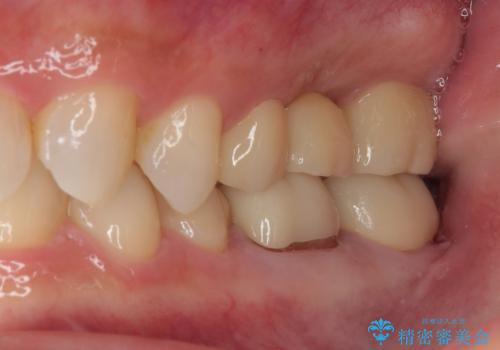

詰め物が欠けた フルジルコニアクラウン

- 詰め物が欠けたとのことで来院された患者様です。来院時特に症状もなく神経の生活反応も確認できました。

詰め物の範囲が大きいためフルジルコニアクラウンによる補綴治療を行いました。

審美面、機能面ともに満足していただけました。

咬み合わせが強い方なので夜間にマウスピースを使ってもらいながら、メインテナンスで通ってもらう予定です。